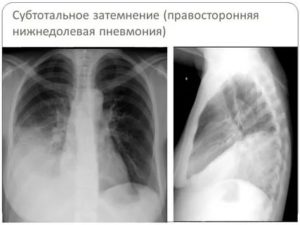

Постановка диагноза производится с использованием инструментальных способов, основным из которых является рентгенография.

При крупозной пневмонии на снимках выявляют усиление легочного рисунка, расширение корня, изменение объема пораженной доли в большую сторону.

При бронхопневмонии отмечается наличие одной или нескольких теней, каждая из которых по размеру не превышает полутора сантиметров. Тени могут сливаться. Рентгенографию проводят в прямой и боковой проекции, что повышает точность исследования.

Рентген снимок нижнедолевой пневмонии